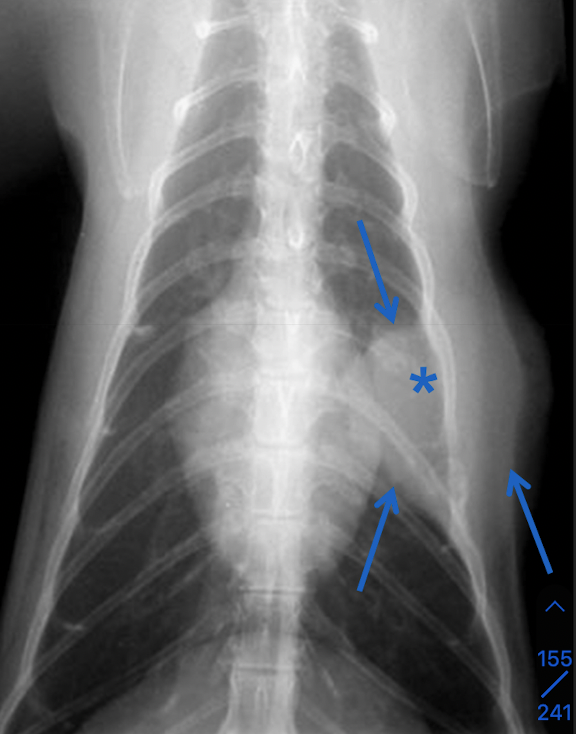

which one pulmonary mass vs extrapleural sign

A

extrapleural sign:

Broad-based mass on the chest wall

Convex shape

Lungs displaced medially

+/- Uneven distances between ribs

+/- Lysis of ribs

Most often neoplasia

How well did you know this?